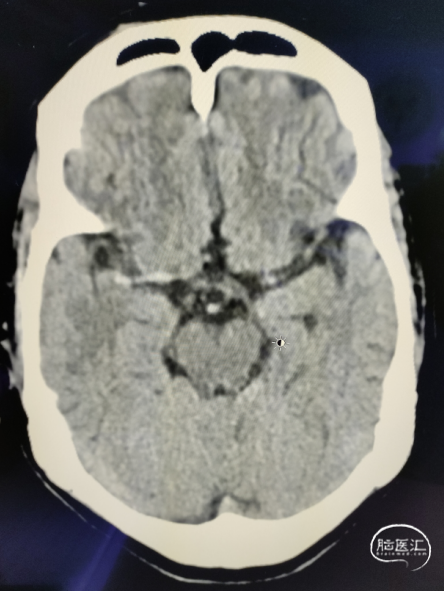

颅脑NCCT见右侧大脑总动脉高密度征,ASPECTS评分10分。

术前

术前造影

造影显示Ⅱ型主动脉弓,RCCA起始段Z字型反向迂曲;RMCA:开口闭塞,TICI分级0级,远端由RACA经皮层支少量代偿,ASITN分级2级。